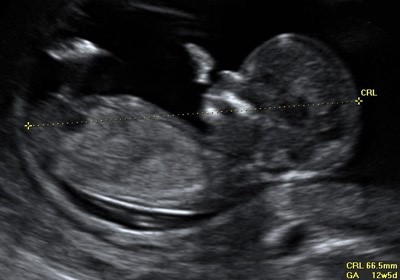

Так проводится измерение копчико-теменного размера плода в первом триместре